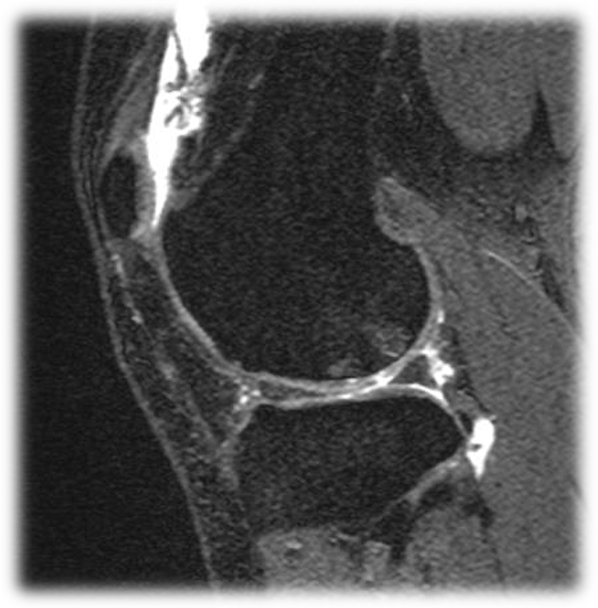

【MRI検査】を積極的に取り入れています。

X線画像には写らない、ひざ軟骨の確認にはMRI検査がかかせません。

MRI画像の白く光っている部分が傷ついた軟骨です。

脊椎や関節(特に膝や肩関節)の痛み・疾患には、

MRI検査をお勧めさせていただきます。